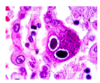

What is the pathological hallmark of CMV infection?

Owl’s eye appearance of lung pneumocytes due to the presence of inclusion bodies